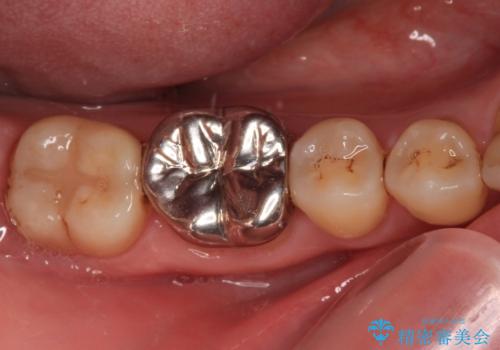

- 人と話す際に、下顎の奥にある銀歯が目立って気になるとのことで来院された患者様です。

左右の奥歯に銀歯のクラウンが装着されていたため、銀歯除去後に仮歯に置き換え、フルジルコニアクラウンにて補綴治療を行うこととしました。